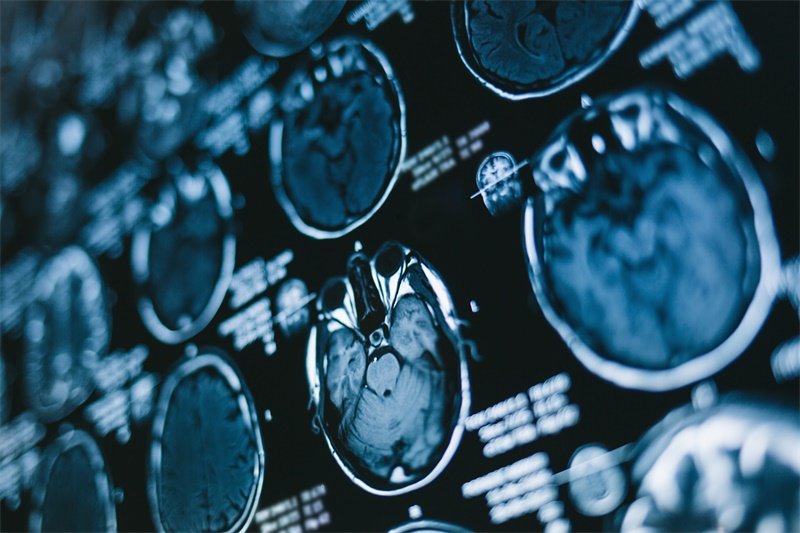

在手术前,我们需要进行详细的术前评估。这通常包括影像学检查(如MRI或CT)和必要的实验室检查。通过这些检查,医生可以更直观地了解病变的性质及其对周围结构的影响。